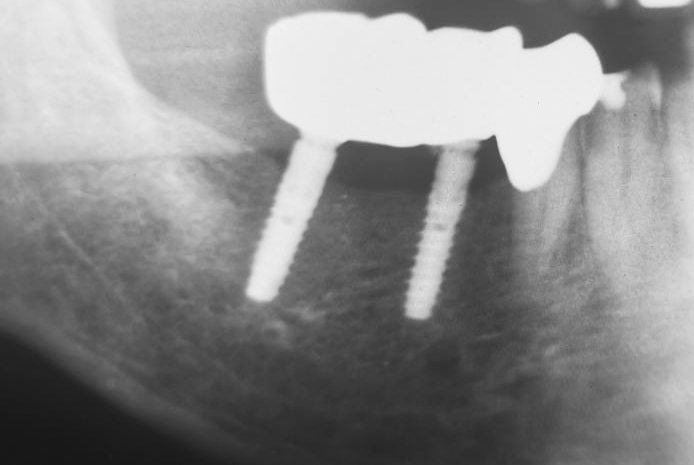

Die Implantate wurden primärstabil und mit der angerauten Oberfläche bis auf Knochenniveau inseriert. Die Röntgenkontrolle belegt eine ausreichende Länge der eingesetzten Implantate BioniQ® Plus.

Die Röntgenaufnahme 14 Monate später belegt ein stabiles, distal des 2,9er Implantats möglicherweise zugenommenes, periimplantäres Knochenniveau.